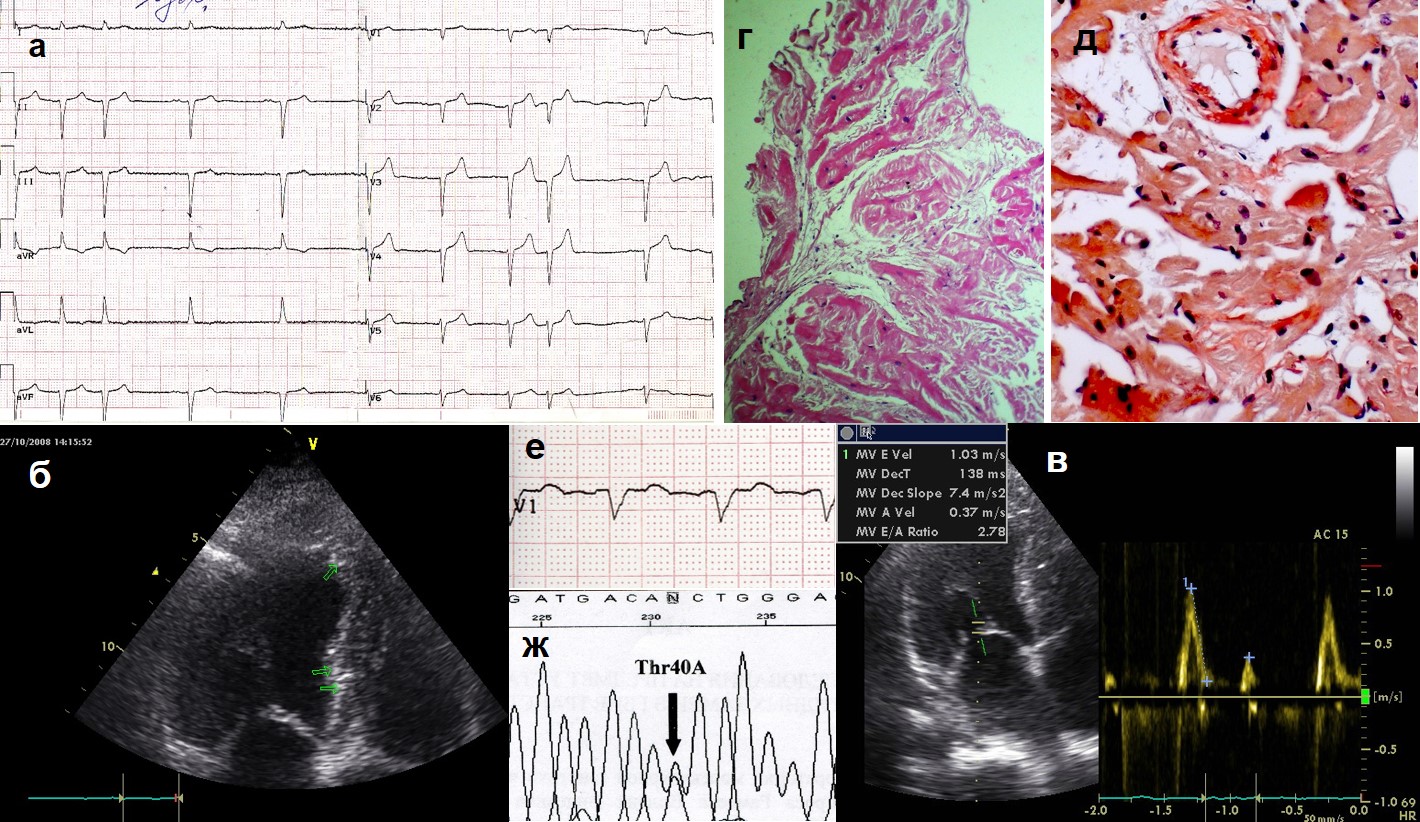

Material and methods. Five 40-79-year old patients with various morphofunctional variants of heart involvement and typical ECG signs (low QRS voltage, QS, non-sufficient R increase, absence of left ventricle (LV) hypertrophy signs) to verify the suspected amyloidosis, underwent EchoCG, immunohistochemistry of blood and urine for light chains of immunoglobulines, biopsy of subcutaneous fat and mucose of the gum/gut; MDCT of the heart (n=3), MRI (n=1), scintigraphy with 99Tc-pyrophosphate with assessment in 1 hour after indicator injection (n=1), endomyocardial biopsy (n=2), titer of anticardial antibodies assessment (n=2), DNA-diagnostics (n=1).

Results. The diagnosis of amyloidosis was confirmed in all cases. Its morpho-functional types were RSMP with LV hypertrophy, hypertrophic cardiomyopathy (HCMP) with no restriction but progressing fall of ejection fraction (EF), dilation cardiomyopathy (DCMP), severe hypertrophy with low EF, minimal hypertrophy with no restriction and systolic dysfunction. There was AL-type diagnosed (n=2, one case with myopathy mimicking “dermatomyositis”), mutant TTR (n=1, novel mutation Thr40Asn) and wild TTR (n=2) types. The leading clinical signs were biventricular heart failure and atrial rhythm disorders: sustained atrial fibrillation in 3 patients (in one, before amyloidosis verification, the RF-modification was done as “labyrinth” surgery, isthmus block with no established efficacy) and frequent supraventricular extrasystoly in one another. To the patient with mutant ATTR the ICD was implanted with further replacement by CRT-D, and increase of EF from 24% to 31% was achieved (patient is followed-up for 8 years). As the morphological equivalent of severe systolic dysfunction in this patient the amyloid deposition in myocardial arteries could be suspected. MDCT revealed typical subendocardial delayed deposition in 2 from 3 patients, in one case there was also diffuse deposition of 99Tc-pyrophosphate in myocardium. Antibodies to the nuclei of cardiomyocytes (specific ANF) was found in a female patient with AL-type and DCMP, which made not to rule out myocarditis.

Conclusion. Cardiac amyloidosis might present as any structural and functional variant of cardiomyopathy, including DCMP. The most specific is diffuse hypertrophy with restriction and EF decrease, but with no LV dilation. Early fall of contractility, ischemia symptoms and LV dilation might be the result of amyloid lesion of small arteries. In the presence of any systemic presentations together with “HCMP”, “RCMP”, “DCMP” there must be amyloidosis ruled out. Myocardial scintigraphy with 99Tc-pyrophosphate is a method of use for the diagnosis of ATTR; MDCT of the heart — for any type of amyloidosis. Cardiac amyloidosis might be followed by significant type of the titer of specific ANF (secondary reaction or concomitance with myocarditis?).